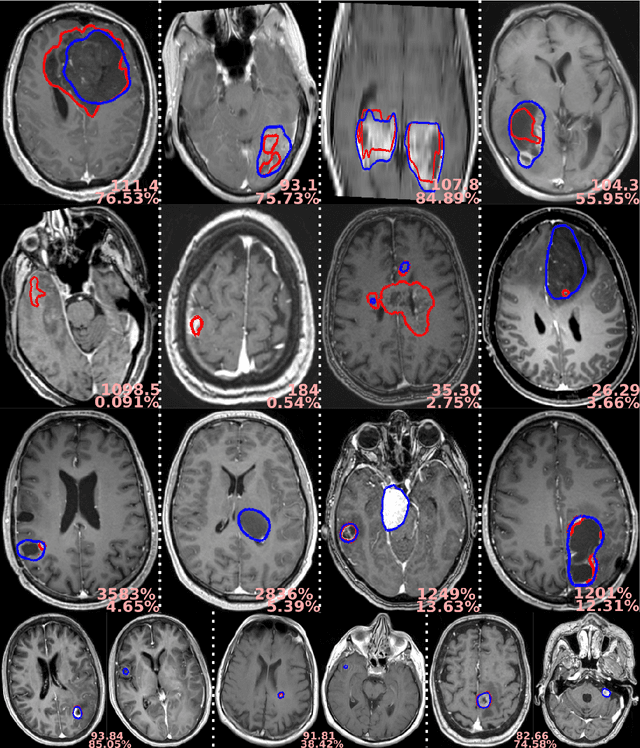

Figure 2 for Preoperative brain tumor imaging: models and software for segmentation and standardized reporting